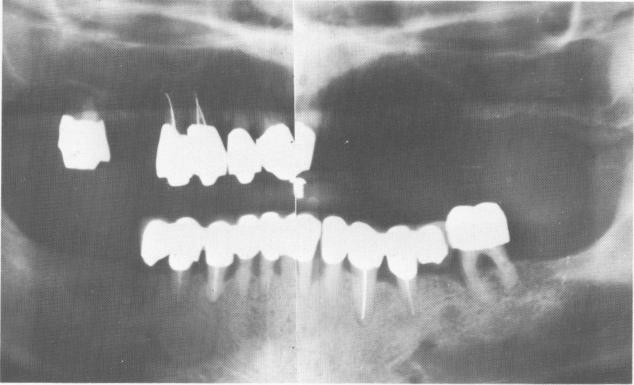

Fig. 15-32. A preoperative Panorex.

1 Preoperative panorex before upper and lower blade implant intervention

The supporting bone in both jaws, except for the bone around the left maxillary bicuspid tooth, was good. However, there was an extremely long edentulous area on the left side and an extremely wide sinus that dropped to the limit of the alveolar